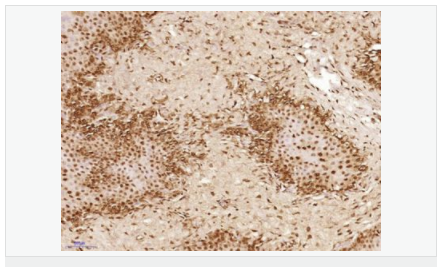

| 產品應用 | IHC-P=1:100-500 IHC-F=1:100-500 ICC=1:100-500 IF=1:100-500 (石蠟切片需做抗原修復) not yet tested in other applications. optimal dilutions/concentrations should be determined by the end user. |

| 細胞定位 | 細胞核 細胞漿 |

| 產品介紹 | This gene encodes a member of the TET family of RNA-binding proteins. The encoded protein plays a role in RNA polymerase II gene transcription as a component of a distinct subset of multi-subunit transcription initiation factor TFIID complexes. Translocations involving this gene play a role in acute leukemia and extraskeletal myxoid chondrosarcoma, and mutations in this gene may play a role in amyotrophic lateral sclerosis. Alternatively spliced transcript variants encoding multiple isoforms have been observed for this gene. [provided by RefSeq, May 2012] Function: RNA and ssDNA-binding protein that may play specific roles during transcription initiation at distinct promoters. Can enter the preinitiation complex together with the RNA polymerase II (Pol II). Subcellular Location: Nucleus. Cytoplasm. Shuttles from the nucleus to the cytoplasm. Tissue Specificity: Ubiquitous. Observed in all fetal and adult tissues. Post-translational modifications: Dimethylated by PRMT1 at Arg-206 to asymmetric dimethylarginine. The methylation may favor nuclear localization and positive regulation of TAF15 transcriptional activity. Phosphorylated upon DNA damage, probably by ATM or ATR. DISEASE: Note=A chromosomal aberration involving TAF15/TAF2N is found in a form of extraskeletal myxoid chondrosarcomas (EMC). Translocation t(9;17)(q22;q11) with NR4A3. Similarity: Belongs to the RRM TET family. Contains 1 RanBP2-type zinc finger. Contains 1 RRM (RNA recognition motif) domain. SWISS: Q92804 Gene ID: 8148 Database links: Entrez Gene: 8148 Human Entrez Gene: 70439 Mouse Omim: 601574 Human SwissProt: Q92804 Human Unigene: 402752 Human Unigene: 181050 Mouse Unigene: 72554 Rat Important Note: This product as supplied is intended for research use only, not for use in human, therapeutic or diagnostic applications. |